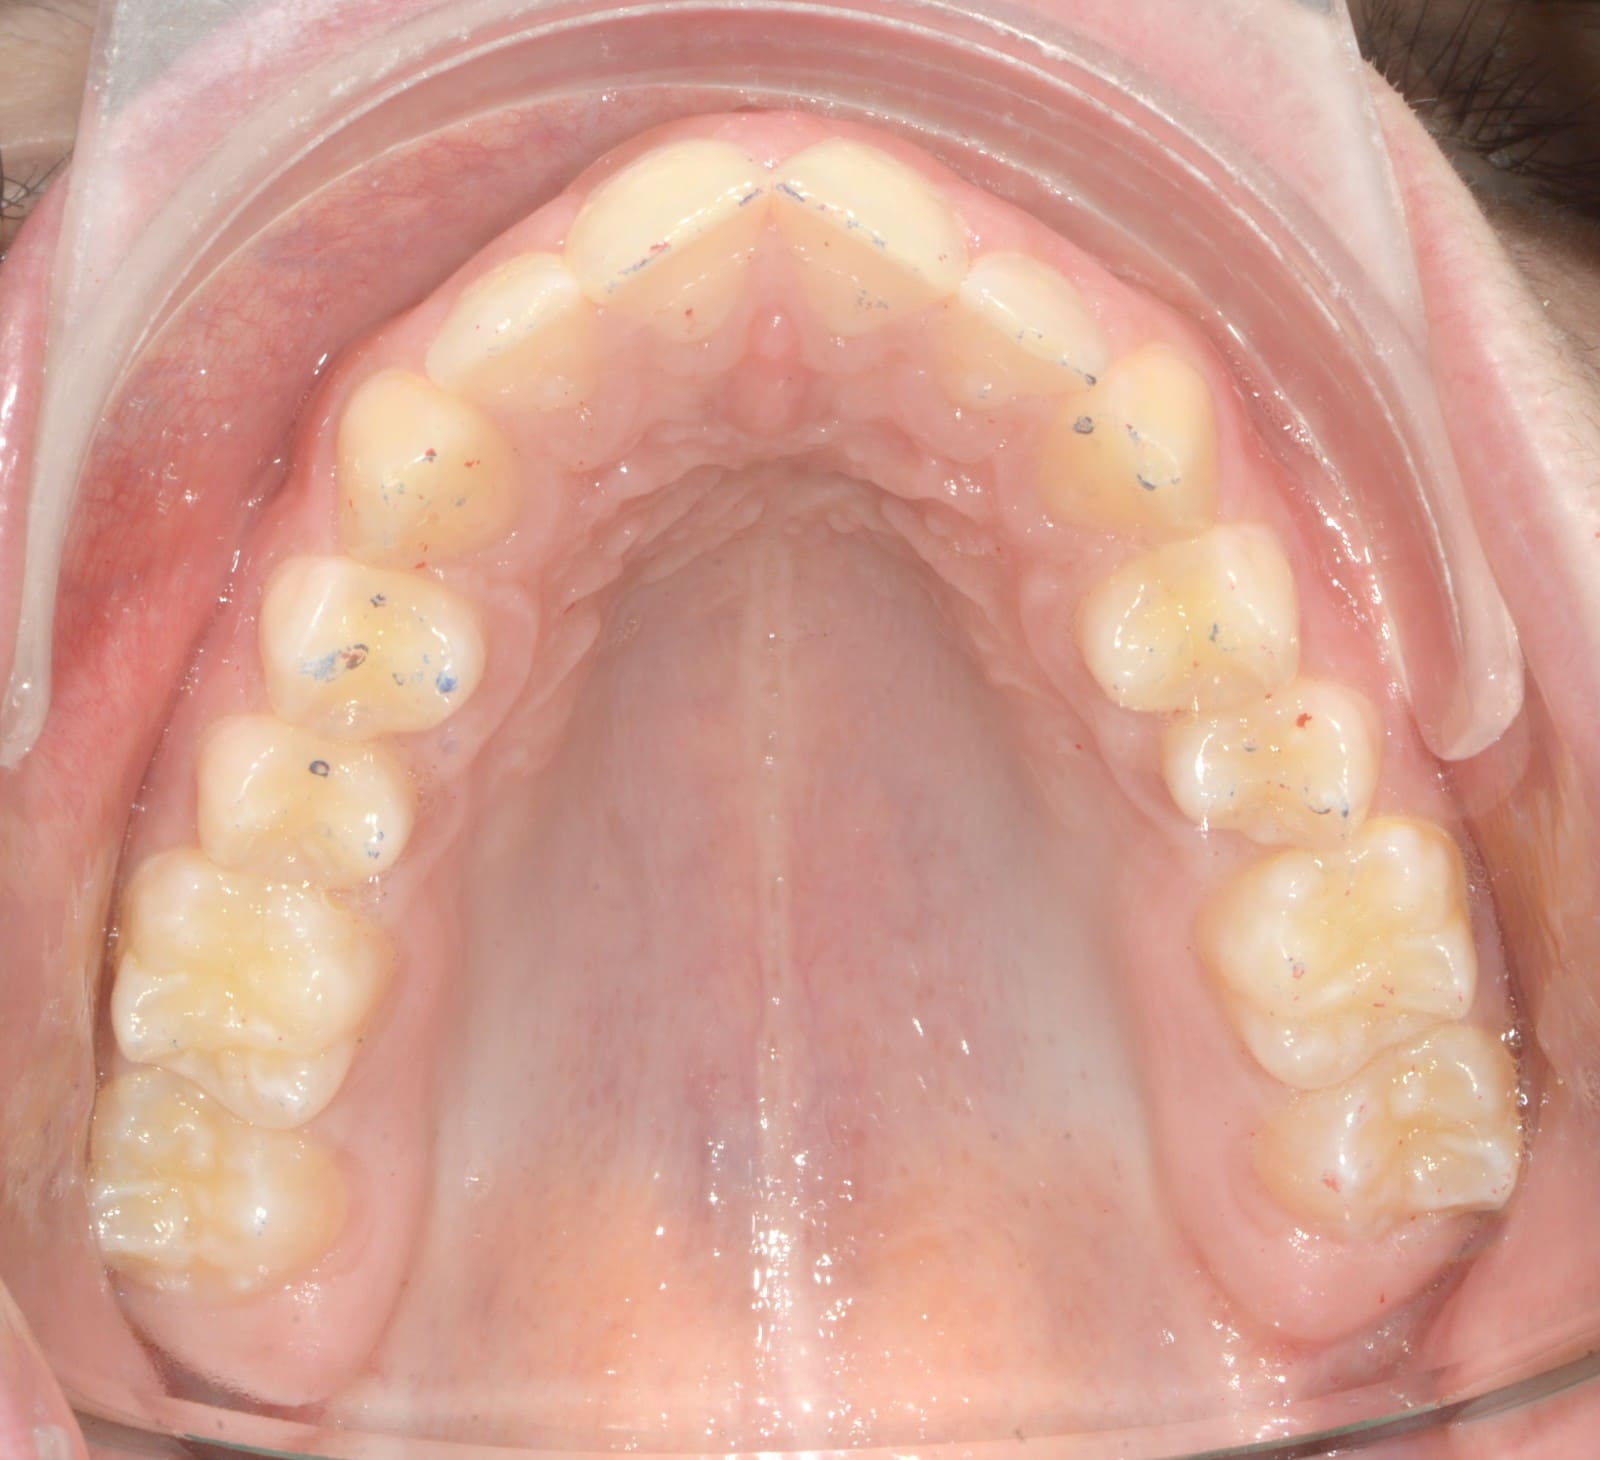

Initial